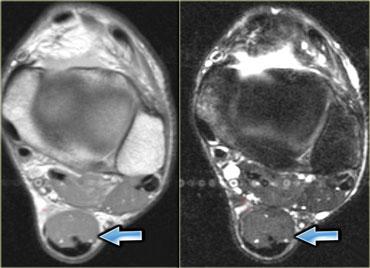

Cơ phụ (Accessory muscles)

Cơ phụ có thể biểu hiện như một khối không triệu chứng, không đau, hoặc kèm theo các triệu chứng chèn ép thần kinh hay chèn ép mạch máu.

Hình bên trái minh họa một trường hợp cơ dép phụ ở mặt trong cổ chân, gây chèn ép thần kinh chày (tức hội chứng ống cổ chân).

Hình bên trái minh họa một loại cơ phụ thường gặp: cơ dép phụ.

Thông thường, cơ dép bám gần như hoàn toàn vào gân Achilles, với một gân dép nhỏ đi phía trước gân Achilles.

Tuy nhiên, ở khoảng 1-2% dân số, cơ dép đi xuống và bám trực tiếp vào xương gót.

Tình trạng này biểu hiện như một khối có thể sờ thấy và thường, nhưng không phải lúc nào cũng, xuất hiện hai bên.

Hình bên trái cho thấy một cơ dép ở vị trí thấp, nhưng không có điểm bám gân riêng biệt vào xương gót.